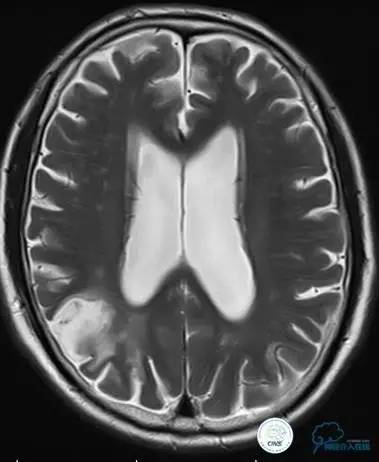

▼术后即刻CT,梗死灶内再灌注出血。

患者无症状,中性治疗。4月21日电话随访,一般情况好,当地CT示出血吸收期。

术后即刻和6天后CT,患者无明显临床症状。

半年后复查造影,无支架内再狭窄,可见弹簧圈,患者恢复至自己柱杖行走。